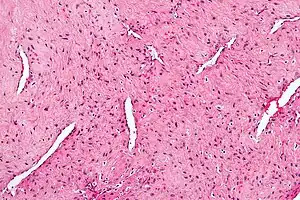

| Micrograph of a nasopharyngeal angiofibroma H&E stain. | |